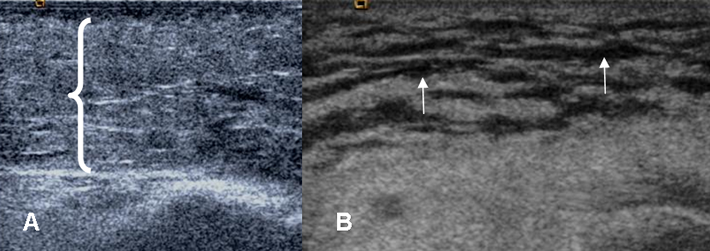

En ecografía hay engrosamiento y aumento de la ecogenicidad de la piel y el tejido celular subcutáneo. Se identifican imágenes lineales y anecoicas que representan líquido en los septos interlobulares, que rodean la grasa hiperecoica, dando el aspecto de mosaico. Este hallazgo es inespecífico y no puede diferenciarse de otras causas. (11, 12). (Fig 11).

Fig 11. Celulitis.

A y B ecografía. Engrosamiento y aumento de la ecogenicidad del tejido celular subcutáneo, por celulitis en A. En B existe patrón de mosaico, con líquido que ocupa los septos interlobulares.